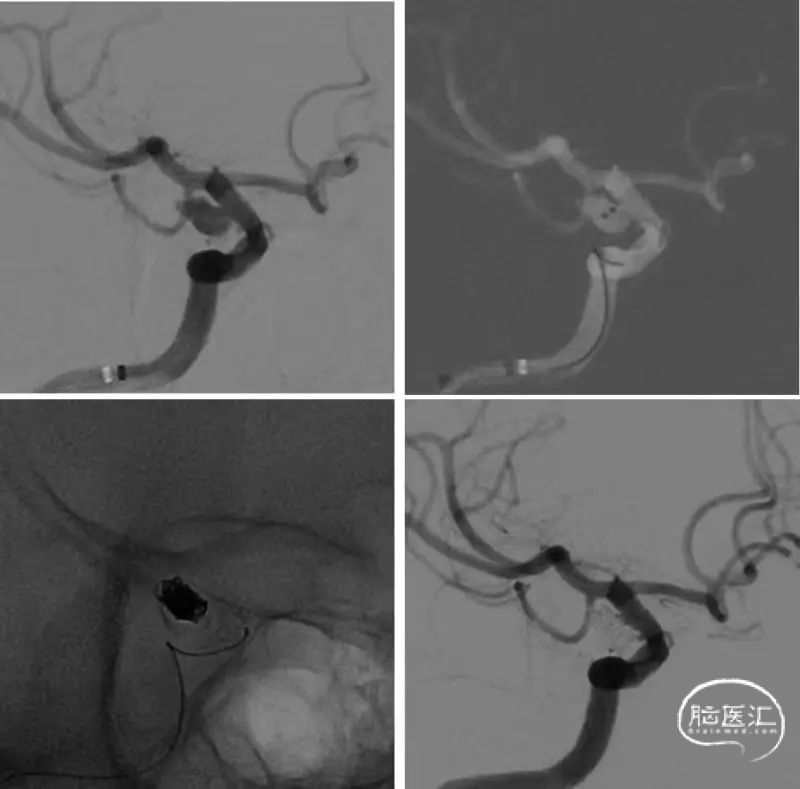

图2

术前讨论

1. 后交通动脉瘤破裂伴较大量出血,患者高龄,有较高的脑积水风险,应尽量避免使用支架。

2. 结合动脉瘤形态和微导管路径,考虑应用双导管栓塞。

3. 必要时可以待出血吸收后行二次支架植入。

操作过程

常规全麻后股动脉入路,Nevien 072到位后,依次将微导管1(SL-10,Stryker )和微导管2(Echelon -10,EV3),置于动脉瘤腔内,管1位于动脉瘤腔中央,管2指向瘤顶部;

管1送入3D弹簧圈成篮(target 5-10),管2送入2D弹簧圈(Axium 3-8)填塞瘤腔顶部。后依次送入弹簧圈3-6,2-4,2-4,1-2填塞,至动脉瘤腔不再显影(mRROC:2)后结束手术。